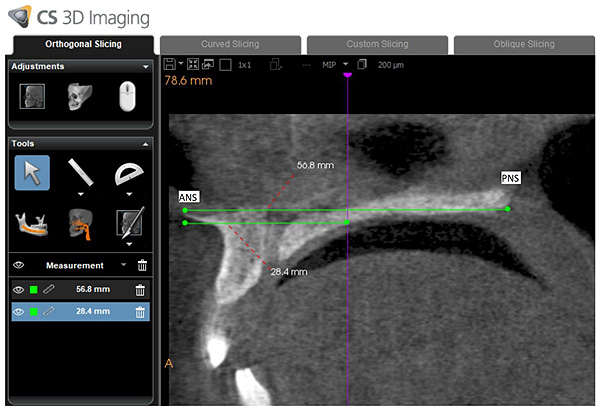

Using dedicated CBCT software (Kodak CS 3D imaging version 3.8.6, Carestream, Rochester, NY, USA), one calibrated oral radiologist (MA) with 12 years of experience with CBCT was responsible for drawing the path of the oropharyngeal airway from the posterior nasal spine to the superior border of the epiglottis on a midsagittal section (Fig. 1). The software subsequently and automatically generated the following values: airway volume (AV: cm3), minimum cross-sectional area (MCA: mm2), minimum anteroposterior distance (MAD: mm), and minimum right to left distance (MRD: mm). In addition to this, airway length (AL: mm) was manually measured by drawing a vertical line connecting the superior and inferior border of the oropharyngeal airway (Fig. 2).

All of the hard palate measurements were obtained on a coronal section at mid-point of the hard palate length. The mid-point is the point located in the middle of the distance between anterior nasal supine and posterior nasal supine in the mid-sagittal plane (Fig. 4).